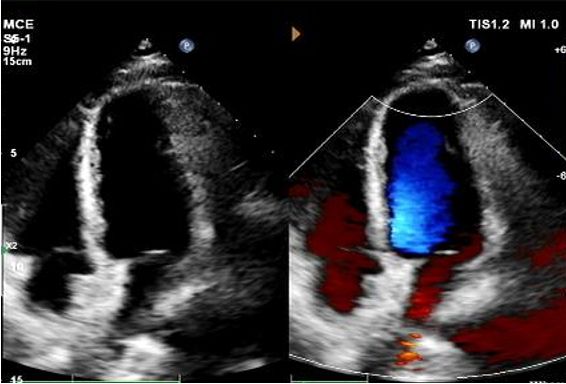

Día 1 a 9 meses:

No se observó derivación residual.

Reducción gradual de la ecogenicidad del dispositivo.

Eco de 1 año:

No visible disc structures – replaced by 8mm tissue thickening at the septal implant site.

Zero residual shunt (rest or post-Valsalva).

Se ha confirmado la absorción completa del dispositivo.